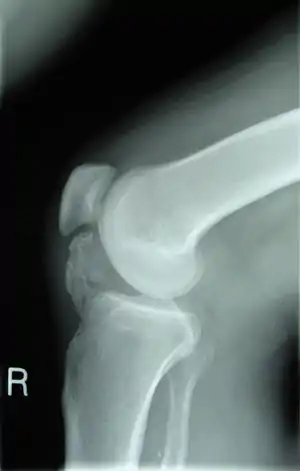

Lateral radiograph of the knee demonstrating ossification in the peritendinous tissues in a patient with osteochondroma.

• X-rays are the first tests performed that characterize a lesion. They show a clear picture of dense structures of bones, and will also indicate bone growth pertaining to osteochondroma.[5][11]